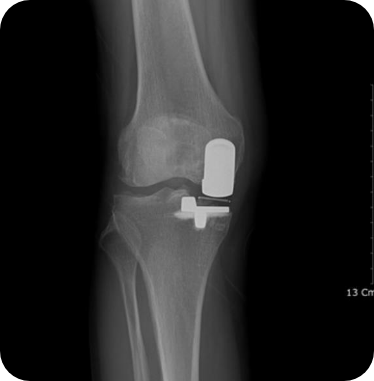

▲ 무릎인공관절 부분치환술 후

• 2) 무릎인공관절 전치환술

무릎의 앞쪽에 10~12cm의 절개를 넣고 무릎 관절 전체를 노출시킨 상태에서 대퇴원위부 및 경골 고평부에 각 뼈의 축에 맞추어 손상된 관절부분을 절제한 후 정해진 기구를 삽입하여 움직임 및 체중부하, 정렬 등에 이상이 없게 만듭니다.

무릎인공관절 전치환술 사례1

• ▲ 수술 전

• ▲ 수술 후